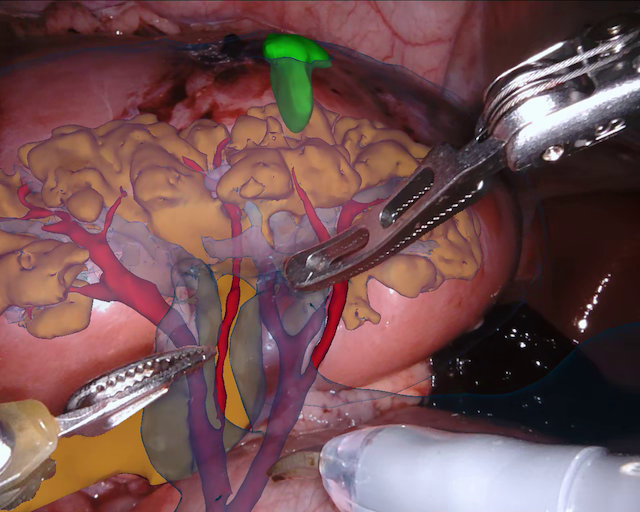

As robotic minimally invasive surgery has developed, with platforms such as da Vinci becoming the de-facto standard-of-care for certain urological, gynecological and general surgical procedures, there has been an increase in focus in how assistive systems based on computer vision and machine learning can improve surgeon performance and patient outcomes. Many potential applications are dependent on scene understanding and for this, accurate segmentation of instruments is an important component. For instance, instrument tracking algorithms which underlie automation and guidance assistance often build upon segmentation [4] or alternatively masking augmented reality overlays of 3D imaging modalities requires pixel labelling of the instruments to prevent their occlusion (see Fig. 1).

Our challenge was made up of 3 sub-problems. The first was binary instrument segmentation, where each frame was separated into da Vinci Xi instruments and a background class, which contained an ultrasound probe, surgical clips and porcine tissues. The second task was instrument part segmentation, where we scored the participants on whether they could correctly segment each articulating part of the instrument (see Fig. 3). Our final task was to segment and classify the instruments (see Fig. 4).